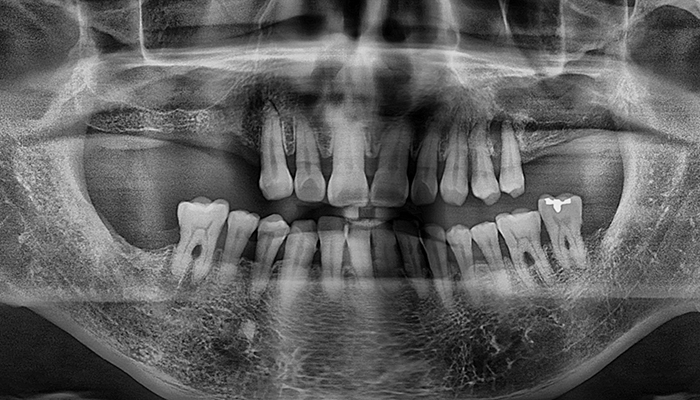

임플란트 수술시, 상악동과 잇몸뼈 사이에 뼈가 남아 있지 않았을 때 상악동막을 들어올리고 빈 공간에 뼈를 이식하여 임플란트 식립을 위한 공간을 확보하는 수술을 상악동 거상술이라 합니다.

밀도가 높고 두꺼운 턱뼈가 구성된 아래턱과는 달리 위턱은 얇은 뼈 위에 코와 광대 사이 빈 공간에 식립해야 하는 고난도 수술로 임플란트 수술 경험이 많은 의료진에게 받는 것이 중요합니다.

치아를 빼고 오래 방치하거나 치아를 잡고 있는 치조골이 많이 녹은상태에서 치아를 빼면 위쪽 턱뼈가 부족할 수 있습니다.